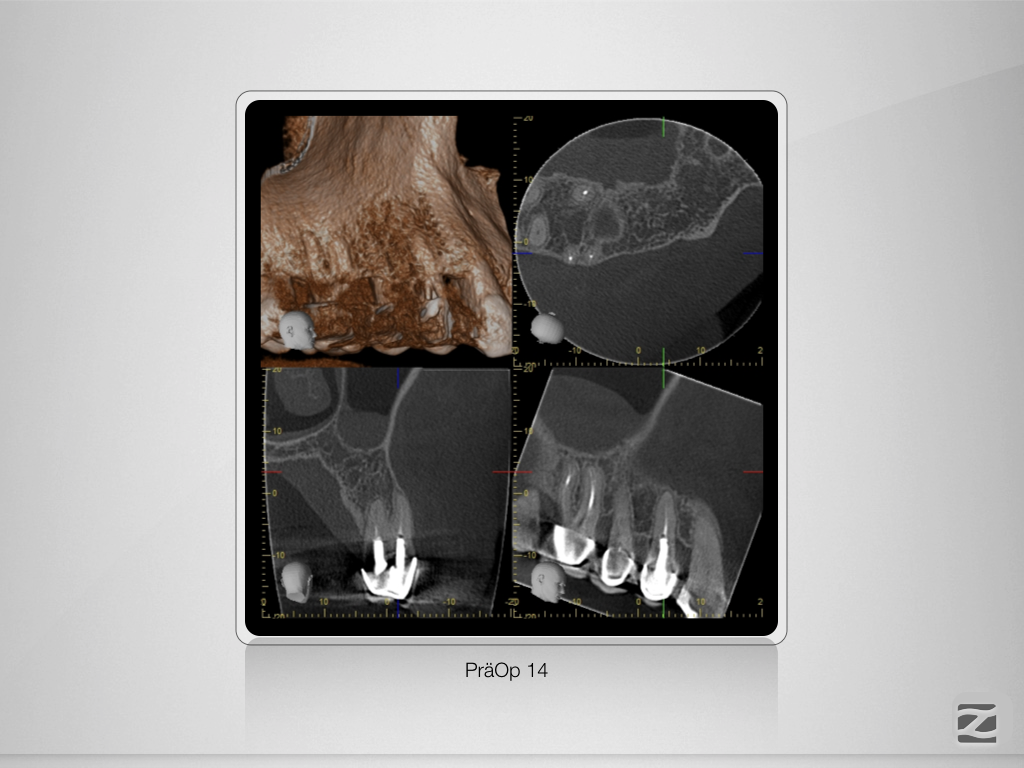

16-14D.004

Mein endodontischer Alltag